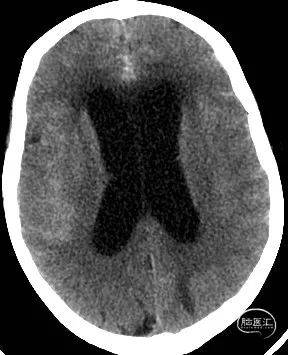

影像检查:CT提示广泛蛛网膜下腔出血(环池、四叠体池、桥前池、桥小脑角、三脑室),Fisher分级2级。CTA提示左侧大脑后动脉P2段动脉瘤,大小约2.3mm*1.3mm,颈宽约2.3mm。

术前CT